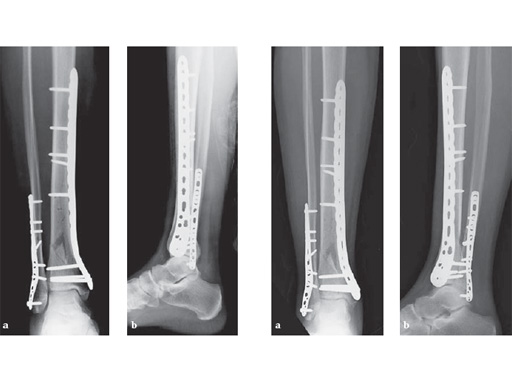

The LCP Medial Distal Tibia (LCP MDT) has a lower profile distally which is optimal for the medial side of the distal tibia where there is often little soft-tissue coverage. Since certain fracture patterns require more distal screw options, the LCP MDT has three diverging distal screws above the joint that capture the anterior and posterior fragments and place the plate more distally. The 3 distal locking head screws diverge across the subchondral bone. The distal locking holes accept 3.5 mm locking head screws, 2.7, 3.5 and 4.0 mm cortex screws.

Additionally, 2 combination holes were added distally in the head of the plate to allow placement of cancellous and cortex screws. These 2 combination holes distally accept 3.5 mm locking head, 3.5 mm or 4.0 mm cortex, or 4.0 mm cancellous bone screws. The distal K-wire hole accepts a 1.6 mm K-wire.

The plate shaft has been widened to 13.5 mm, which is comparable to a narrow LC-DCP 4.5. At the proximal end of the plate, an articulated tension device (ATD) hole was added to allow for compression and distraction

using the articulated tensioning device.

29-year-old female after a motor vehicel crash

Case provided by Sean Nork, Washington, USA

The fibula was reduced and stabilized through a posterolateral surgical approach. A small anterior incision was used to apply multiple clamps and to access the fracture reduction. A medial locked distal tibial plate was placed adjacent to the anteromedial surface of the tibia through a 4 cm distal incision. Multiple proximal screws were placed through small incisions overlying the plate.